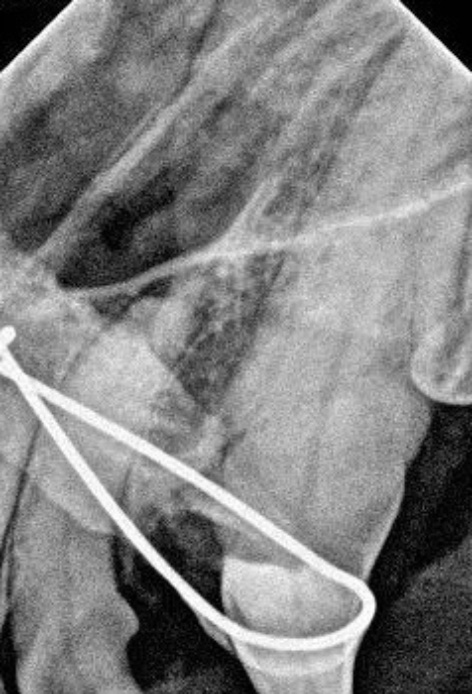

Figure 3. Postoperative dental radiograph after reduction and fixation in the affected dog

3. 患犬复位固定术后牙片

术中复位时间约15分钟。复位后立即拍摄牙片确认牙根位置正常、牙槽间隙恢复(图3)。